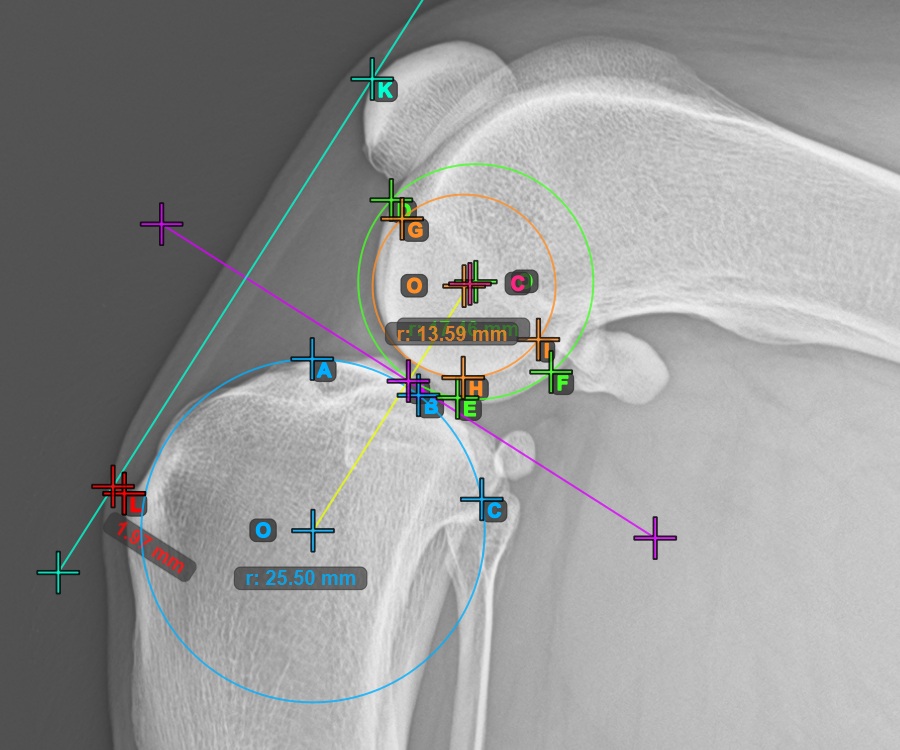

Kezdje el a mérést a három pont megjelölésével a Condylus Medialis Tibialis-on.

Jelölje meg a három pontot a tibia fő condylusán (Medialis Tibialis). A sorrendtől függetlenül ügyeljen arra, hogy megjelölje a legfelső pontot, a legalacsonyabb pontot és a Medialis Tibialis középpontját. A három pont alapján a rendszer automatikusan létrehoz egy kört.

A lenti kép a Condylus Medialis Tibialis-on elhelyezett három pont tipikus elhelyezkedését ábrázolja.